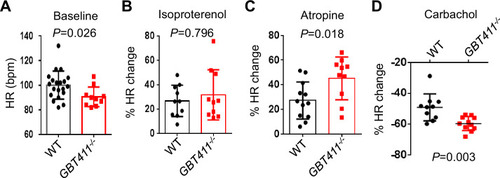

The GBT411 mutant displayed aberrant response to autonomic stimuli. Shown are changes of HR in GBT411-/- homozygous fish at 16 months in response to different autonomic stimuli. N=9–20 animals per group, unpaired student’s t-test. |